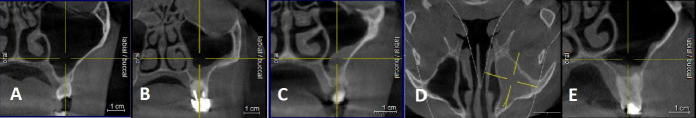

Results: Significant differences were found in sinus width between patients with full dentition and those with partial or complete edentulism (p<0.01). Male participants exhibited larger mean sinus dimensions compared to females in all dimensions. The maxillary sinus floor was inferior to the nasal floor in 91.5% of cases. Various types of sinus membrane abnormalities were observed, with normal membrane thickness in 53.75% of cases. Sinus septa were most frequently located on the roof of the sinus, and their frequency varied significantly among patients with different dentition statuses. The study also identified 274 Haller cells and documented several pathological changes, with mucosal thickening exceeding 3 mm being the most common alteration.